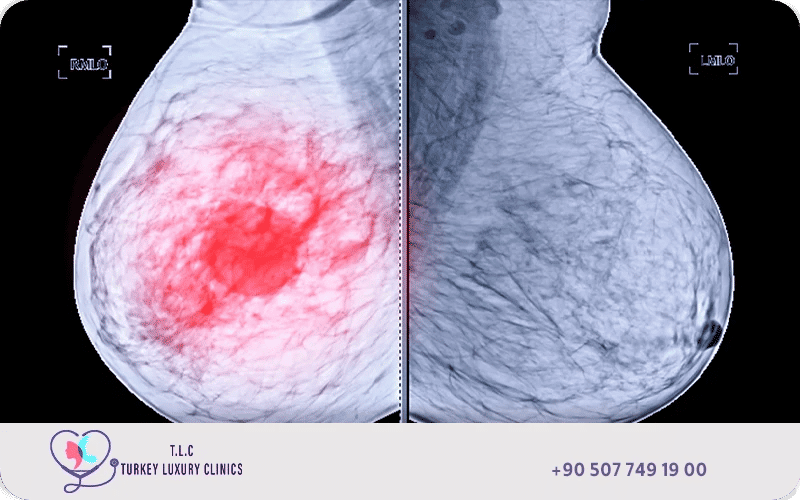

التصوير الشعاعي (الماموغرام)

يُعد من أهم وسائل الكشف المبكر عن سرطان الثدي، حيث يكشف التغيرات الدقيقة أو الكتل الصغيرة قبل ظهور الأعراض الواضحة، وينصح الأطباء بضرورة التصوير بالماموغرام قبل سن ال40 للكشف المبكر عن سرطان الثدي.

يتضمن تشخيص سرطان الثدي سلسلة من الفحوصات الدقيقة، أبرزها تصوير الماموجرام، والأشعة فوق الصوتية، والرنين المغناطيسي, إلى جانب الخزعة وهي الطريقة الحاسمة والأدق للكشف عن وجود ورمٍ خبيث في الثدي, إليك طرق تشخيص سرطان الثدي: